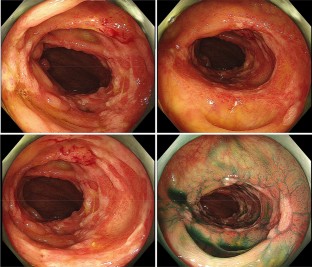

Lenvatinib is a standard molecular targeted agent for the first-line treatment of unresectable hepatocellular carcinoma. Here, we report a case of colitis induced by Lenvatinib treatment in a patient with hepatocellular carcinoma. A 78-year-old man previously treated with Lenvatinib for unresectable hepatocellular carcinoma was admitted to our hospital complaining of right lateral abdominal pain without diarrhea. Our endoscopic findings showed multiple ulcers and erosions on his ascending colon, and he was diagnosed with colitis induced by Lenvatinib treatment. After the discontinuation of Lenvatinib, his colitis improved, and he resumed Lenvatinib at a lower dose. Colitis is a rare adverse event of Lenvatinib, and this is the first detailed report of colitis induced by Lenvatinib with endoscopic findings.

Fig. 2